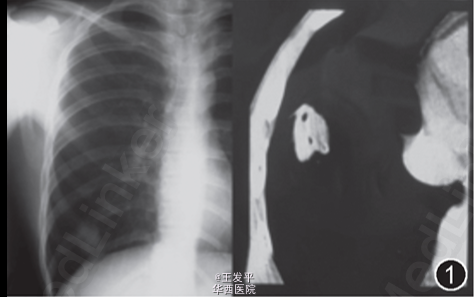

查体:胸廓对称,双肺叩诊音清,右下肺呼吸音粗糙,双肺未闻及干湿啰音。余未查见特殊 辅助检查:X线胸片示右下肺占位性病变,胸部CT示右肺下叶基底段类圆形阴影,约24mm×28mm大小,内有不规则透亮影,周边有毛刺,胸膜有牵拉,周围肺纹理粗乱,临近叶间胸膜增厚,纵膈未见淋巴结肿大。血常规无异常,血包虫抗体阴性,痰3次抗酸染色和细菌培养无特殊,痰中未发现包虫虫体或头钩。

考虑肺包虫病不能除外。 处理:行右肺下叶楔形切除术。术中切开肿块发现完整包囊2层,内壁光滑,囊内无明显内容物,外囊与周围肺组织界限清。术后病理提示肺包虫病合并曲霉菌感染。 术后诊断:右肺下叶肺包虫病合并曲霉菌感染